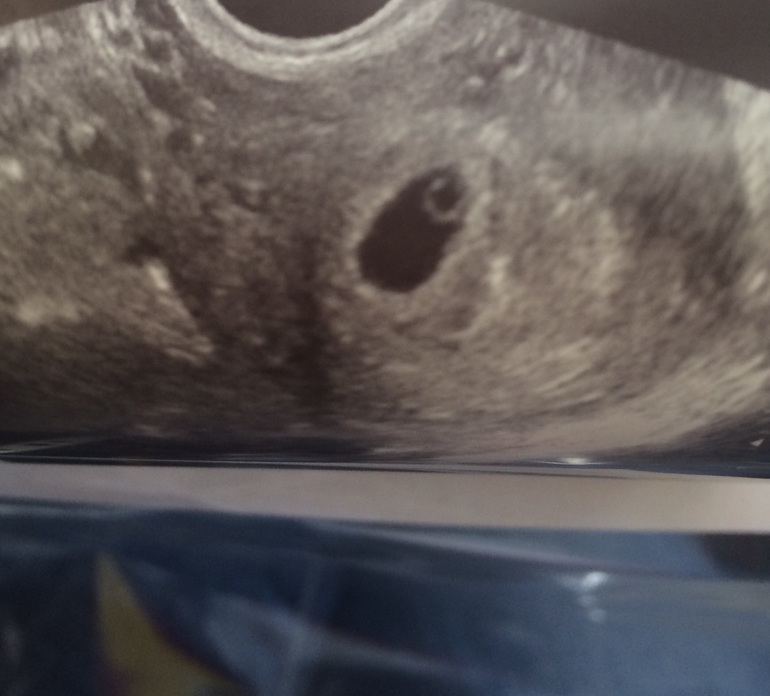

Наше первое фото)

Красота! У меня последние месы начались 7 мая, иду на узи в субботу и еще пока не надеюсь, что увидять малявочку, хоть бы пока внематочную исключить. Как дожить))). Для имбриона рано еще, не переживайте раньше времени

У меня на 2 недели эмбриональных и (4 акушерских) ПЯ 4 мм было и желточный мешочек там,сказали придти через пару недель и посмотреть уже эмбриончика)так что терпите;)я тоже жду этого дня чтоб увидеть)))

У меня эмбрион увидели в 6 с чем то акушерских, а сердцебиение и того позже, так что запаситесь терпением:) я для своего успокоения сдавала ХГЧ в динамике, плотное яйцо нормальное у Вас так что ждите:)

у меня когда была берем срок от начала месячных 43 дня (медик аборт) было плодное яйцо 12 мм и никто не говорит на таком сроке про эмбрион. эмбрион позже видно! насколько знаю к 6 -7 неделе берем

Просто Узист стал грить что для трех недель плодное яйцо большое, а я б физически раньше не смогла забеременеть, у меня ток задержка 4 дня. Самое главное, оно нашло местечко. Ждем ХГЧ и анализируем)